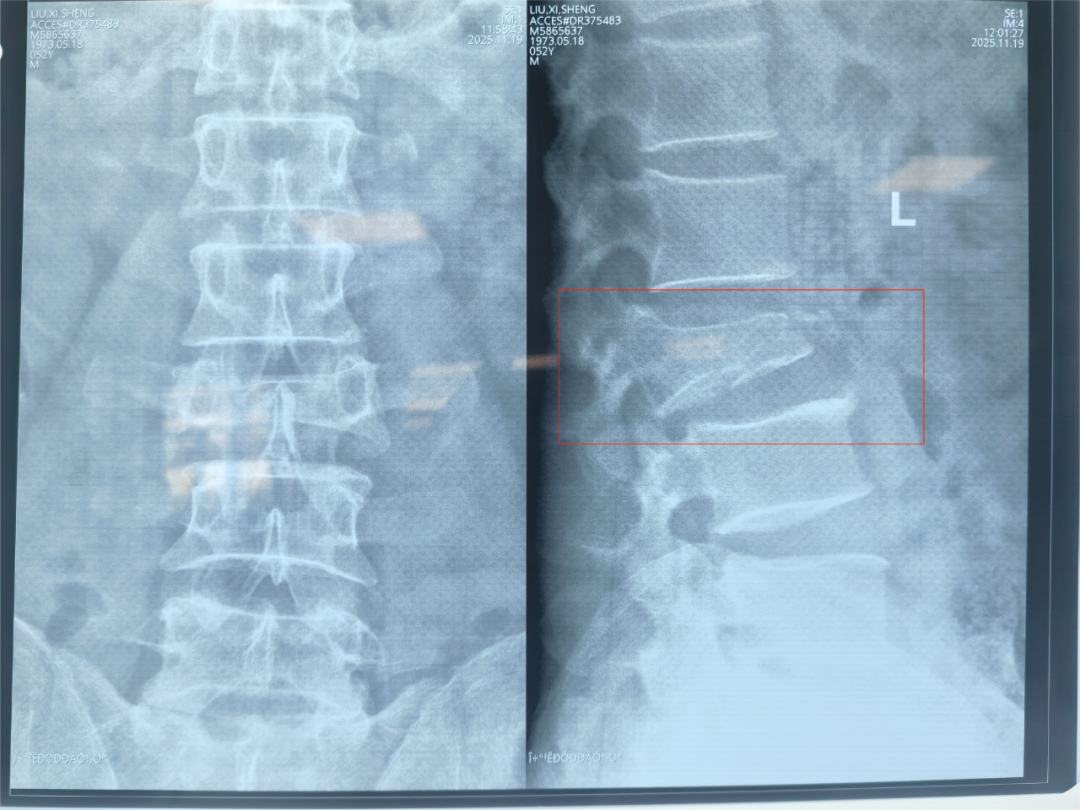

该患者为一名52岁中年男性,在工作时不慎从高处坠入3米深坑中,重伤腰部,被紧急送至西安市中心医院经开院区急诊科。急诊科请骨科张强医师紧急会诊,张强医师对患者进行详细查体后,第一时间要求完善患者相关腰椎X线、腰椎CT三维重建及腰椎MRI等检查,及时向刘邦定主任进行汇报,入院时,患者双下肢已完全不能活动,感觉减弱,情况万分危急。经过紧急CT及核磁共振检查,被确诊为“腰3椎体爆裂性骨折伴不全瘫痪”,碎裂的骨块如同“炸弹的弹片”一样,严重侵入椎管,压迫了支配下肢感觉和运动的脊髓神经。这正是导致患者瘫痪的直接原因。